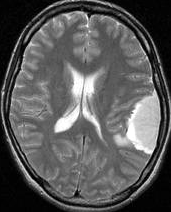

MRIでの髄膜腫の見え方は撮影の仕方によっていろいろです。左からT1強調画像,T2強調画像,フレア画像といいます。腫瘍の横に小さく白い領域がありますが,これは脳の腫れた部分で脳浮腫といいます。髄膜腫があると周囲に脳浮腫が生じることがあります。

- T2強調やフレア画像では,腫瘍周囲に強い脳浮腫(脳が腫れる)があることも多いです

- CTで腫瘍の石灰化がある,T2強調画像で低信号(黒っぽい)ものは大きくならない傾向があります